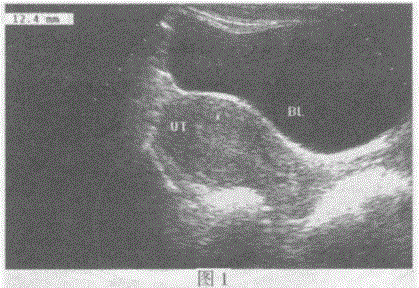

问题 图1临床资料:女性,32岁,常规体检。 超声综合描述:经腹扫查子宫形态、大小正常,肌层回声均匀,子宫内膜居中,厚度1.2cm。请指出图中子宫位置: 图2临床资料:女性,37岁,常规体检。 超声综合描述:经阴道扫查子宫形态、大小正常,肌层回声均匀,子宫内膜居中,厚度0.6cm。请指出图中子宫位置: 超声提示:

选项 A.图1:水平位子宫图2:前位子宫 B.图1:前位子宫图2:后位子宫 C.图1:后位子宫图2:水平位子宫 D.图1:子宫脱垂图2:子宫脱垂

答案 B